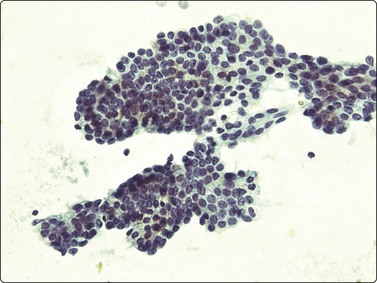

Embryonal carcinoma (Figs 13.33 and 13.34)14,58-61,63,65,66

Fig. 13.33 Embryonal carcinoma

(A) Adenocarcinoma-like tissue fragment of large malignant cells with large vesicular nuclei, coarse chromatin, prominent nucleoli; prominent cytoplasmic vacuolation (MGG, HP); (B) Fragment of undifferentiated mesenchymal tissue right; cluster of malignant epithelial cells with large vesicular nuclei and prominent large nucleoli (H&E, HP) left.

Criteria for diagnosis

Cell-rich smears,

Frequent three-dimensional clusters,

Occasional tendency to acinar and microglandular grouping,

Large vesicular, obviously malignant nuclei, large nucleoli,

Indistinct cell borders,

Basophilic to amphophilic, sometimes pale, vacuolated cytoplasm,

Immunocytochemistry: cells positive for PLAP, OCT 3/4, CD30, AE1/AE3 and CK7.

The vesicular nuclei of embryonal carcinoma are larger and more pleomorphic than those of seminoma, the chromatin is coarse and irregular and nucleoli are large, occasionally huge, and eosinophilic. The cytoplasm is pale and distinctly vacuolated, but not ‘bubbly’. It is not highly fragile and a TB as in seminoma is not seen. Cytoplasmic boundaries are poorly defined (Fig. 13.33). Hemorrhage and tumor necrosis may be prominent and may hamper the identification of diagnostic cells. It is usually not seen in smears of seminoma. Chromatin threads and reticulated material resembling TB can occur. Large syncytiotrophoblastic cells may be found. Prominent lymphoid/plasma cell infiltrates or mucus are not seen. The presence of cellular mesenchyme on its own does not warrant a designation of teratoma (Figs. 13.33B and 13.34).49